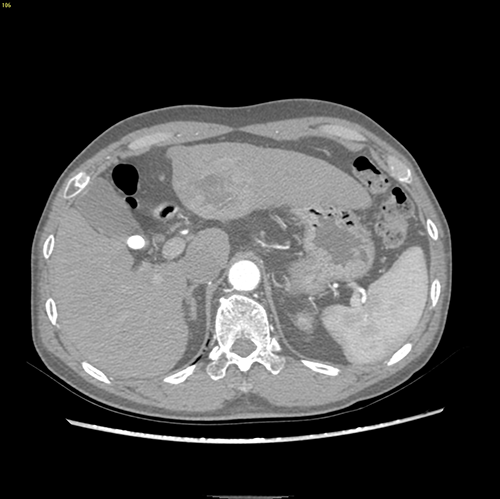

左肝外侧叶肝癌---左肝外侧叶切除